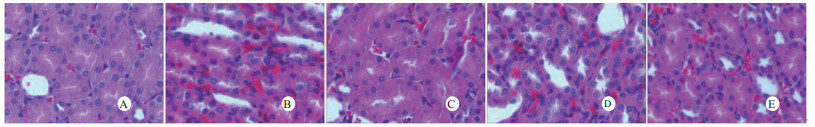

光镜下可见,假手术组肺泡大小形态均匀,结构清晰,肺泡腔内无出血和白细胞浸润;感染性休克组肺泡壁破坏严重,血管壁和肺泡间隔明显增厚;U50488H+感染性休克组大部分肺泡腔均匀一致,肺间隔略增厚,肺泡壁轻度水肿,但出血和白细胞浸润情况比感染性休克组明显减轻(图 1)。假手术组心肌细胞大小一致,排列整齐,核浆比正常,心肌细胞核呈椭圆型,胞浆均匀红染;感染性休克组心肌细胞肿胀,体积明显增大,细胞核大而异型,核内染色质固缩、边集,白细胞浸润明显增加;U50488H+感染性休克组多数心肌细胞形态相对正常,少数心肌细胞呈现脂肪变性(图 2)。假手术组肝细胞结构完整,肝小叶形态正常;感染性休克组肝细胞显著肿胀、呈空泡样和点状/小片状坏死;U50488H+感染性休克组肝细胞轻度肿胀,未见明显坏死灶、肝血窦扩张和炎性细胞浸润(图 3)。假手术组肾组织结构大致正常;感染性休克组肾小管细胞轻度水肿、空泡变性;U50488H+感染性休克组肾小管形态大致正常,间质无明显出血水肿(图 4)。

| A:假手术组,B:感染性休克组,C:U50488H+感染性休克组,D:nor-BNI+U50488H+感染性休克组,E:nor-BNI+感染性休克组 图 2 各组光镜下心肌组织病理学改变(HE×400) Fig 2 Histopathological features of myocardium(HE×400) |

本研究还进一步观察了感染性休克大鼠重要脏器的病理学变化与超微结构。结果发现,感染性休克时,肺泡壁破坏严重,血管壁和肺泡间隔明显增厚,炎症细胞浸润较多,肺泡明显压缩畸形,肺泡隔肿胀,扭曲,隆起。该结果与潘景业等的报道一致。同时实验发现,U50488H可减轻感染性休克肺泡壁出血水肿与肺组织炎性细胞浸润,抑制肺间隔增厚。实验还观察到感染性休克大鼠心肌纤维肿胀、扭曲、断裂、溶解,并由此导致心功能障碍。U50488H亦可减轻线粒体肿胀崩解和心肌细胞溶解与坏死,可能与U50488H减轻心肌抑制有关[12],具体机制与分子通路尚需进一步实验验证。本研究还观察到感染性休克大鼠肝细胞出现肿胀、空泡样脂肪变性和点状/小片状坏死,毛细胆管明显增多、扩张;肾小管细胞轻度水肿、空泡变性,肾小管上皮细胞微绒毛缺失,细胞崩解,肾小管上皮断裂。预先给予U50488H可显著减轻感染性休克肝细胞浊肿、肝血窦扩张和炎性细胞浸润;抑制肾小管上皮细胞核变形、微绒毛坏死和间质出血水肿。nor-BNI可阻断这一效应。上述结果均提示U50488H可通过激动κ-阿片受体,改善肝脏和肾脏血流量保护感染性休克肝脏和肾脏功能,具体机制可能和细胞凋亡等相关。